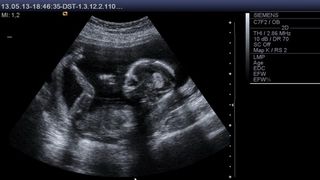

Nu mică le-a fost surpriza medicilor atunci când o femeie s-a dus să nască din nou, la numai 26 de zile de la naștere.

Arifa Sultana, 20 de ani, a născut gemeni la numai 26 de zile după ce ieșise din maternitate. Explicația este una cât se poate de plauzibilă, femeia avea două utere, însă medicii nu au observat asta atunci când Arifa a mers să nască prima oară.

Pentru cea de-a doua sarcină, medicii au intervenit de urgență printr-o operație de cezariană și femeia a adus pe lume gemeni, un băiat și o fată.

La numai câteva zile dupa cea de-a doua naștere, femeia a părăsit spitalul cu toți cei trei copii, fără a avea complicații post-operatorii, însă deschis o investigație cu privire la faptul că spitalul unde s-a aflat tânăra nu a detectat a doua sarcină atunci când au ajutat-o să nască prima dată.